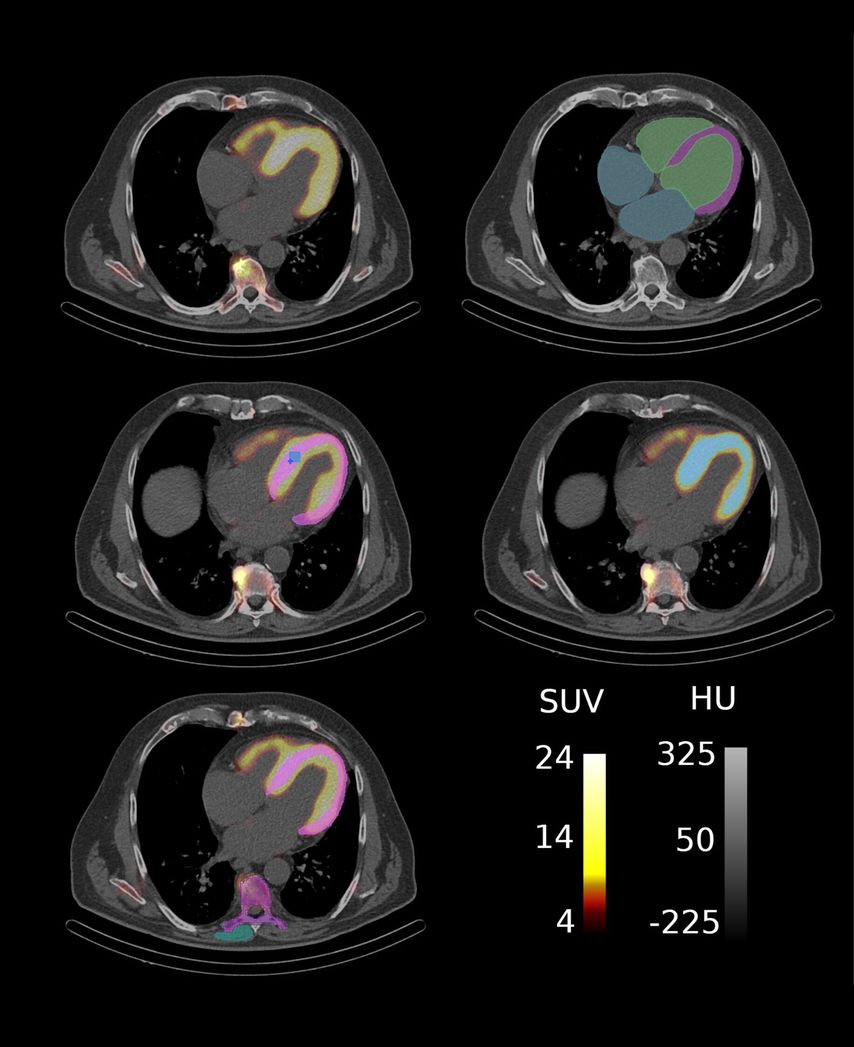

Im Rahmen einer explorativen bildgebenden Studie der Klinischen Abteilung für Kardiologie in Kooperation mit der Klinischen Abteilung für Nuklearmedizin der Medizinischen Universität Wien wurde der Einfluss amyloidspezifischer Therapien auf SPECT/CT-basierte Marker untersucht (Abb. 2), die myokardiale Amyloidablagerungen widerspiegeln. Die KI-gestützte Segmentierung der kardialen Strukturen ermöglicht eine umfassende Quantifizierung der Amyloidablagerungen im Myokard und können als potenzielle nichtinvasive bildgebende Biomarker zur Überwachung der therapeutischen Wirksamkeit bei Patient:innen mit ATTR-CM dienen (Abb. 3).

Die Studienkohorte umfasste 45 Patient:innen mit ATTR-CM, die eine amyloidspezifische Therapie, wie TTR-Stabilisatoren (Tafamidis) oder TTR-Silencer (Patisiran, Inotersen), erhielten und sich sowohl vor Therapiebeginn als auch nach neun Monaten im Rahmen eines Follow-ups einer SPECT/CT-Bildgebung unterzogen. Die KI-gestützte Segmentierung der kardialen Strukturen erfolgte mithilfe eines Deep-Learning-Modells, das die automatisierte Extraktion von 23 quantitativen Markern ermöglichte, darunter Intensitäts- und Volumenmarker des Tracer-Uptakes sowie der Retentionsindex über verschiedene kardiale Substrukturen. Darüber hinaus wurden funktionelle Parameter – einschließlich klinischer und laborchemischer Variablen – sowie klinische Endpunkte hinsichtlich ihrer Assoziation mit Veränderungen der SPECT/CT-Marker vor und nach der Behandlung untersucht.

Abb. 2: ATTR-CM Patient mit Segmentierungsmasken für myokardbasierte Marker: (a) SPECT/CT Aufnahme, (b) CT-Aufnahme mit Basis-Segmentierungen, (c) Segmentierung zur Extraktion klassischer SUV-Parameter wobei SUVpeak in Hellblau und SUVmax in Dunkelblau dargestellt ist, (d) Segmentierung des Amyloid-assoziierten Volumens und (e) Segmentierungen für den Retentionsindex. (Quelle: eigene Anfertigung)

Im Therapieverlauf zeigten sich signifikante Reduktionen bei 14 von 16 (88%) SPECT/CT-Markern, insbesondere eine deutliche Abnahme der Tracer-Aufnahme im linken Ventrikel und Myokard. Diese Veränderungen korrespondierten mit Verbesserungen funktioneller Parameter. So war ein reduzierter NT-proBNP-Wert mit einer geringeren Tracer-Aufnahme assoziiert, insbesondere in Bezug auf den SUVpeak-Wert des Myokards und den SUVmax-Wert des Myokards, des rechten und des linken Ventrikels. Darüber hinaus ging eine Reduktion des Retentionsindex mit einer Verbesserung der „New York Heart Association (NYHA)“-Klasse einher. Angaben zu herzinsuffizienzbedingten Hospitalisierungen (HFH) lagen für 30 von 45 (67%) Patient:innen vor, von denen 9/30 (30%) ein Ereignis nach einem medianen Follow-up von 34,9 Monaten aufwiesen.

Die Studie unterstreicht den Nutzen der KI-gestützten SPECT/CT-Bildgebung zur Erfassung therapieinduzierter Veränderungen der kardialen Amyloidlast bei Patient:innen mit ATTR-CM. Die automatisierte Markerextraktion durch KI reduziert die Variabilität zwischen Auswerter:innen, erhöht die Effizienz und verbessert die Reproduzierbarkeit. Die Ergebnisse verdeutlichen das Potenzial von SPECT/CT-Markern als sensitive, nichtinvasive Bildgebungsbiomarker zur frühen Beurteilung des Therapieansprechens und bieten damit eine Alternative zur kardialen Magnetresonanztomografie bei ATTR-CM-Patient:innen mit implantiertem Schrittmacher oder Defibrillator. Diese Erkenntnisse ebnen den Weg für personalisierte Behandlungsstrategien und eine breitere klinische Anwendung von KI in der Nuklearmedizin.